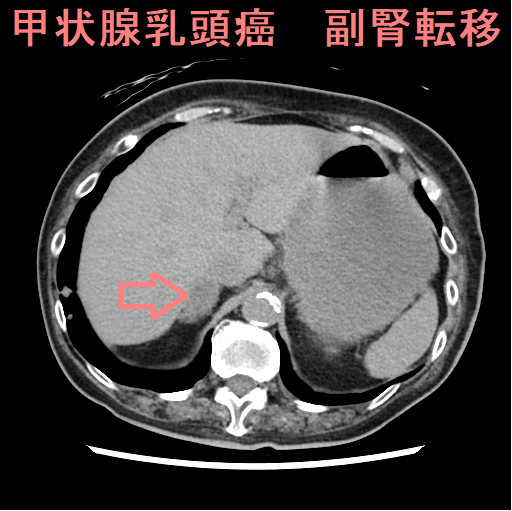

転移性副腎腫瘍は肺癌などの副腎転移が多く、超音波検査で低エコー、副腎出血に至る事も。手術適応は少なく、切除後の予後は不変。甲状腺乳頭癌の副腎転移は癌死後の剖検で見つかる事が多く、存命中に見つかるのは稀。副腎の悪性リンパ腫は周囲からの転移性がほとんど。副腎原発悪性リンパ腫(PAL)は稀で両側性が多く、自己免疫疾患合併率が高い、副腎不全・中枢神経浸潤も起こしやすい。副腎皮質癌は稀でLi-Fraumeni症候群の合併が多く、癌抑制遺伝子・p53遺伝子と関連。副腎皮質癌のホルモン産生は60%で、コルチゾール産生するクッシング症候群が最多。

甲状腺分化癌(乳頭癌・濾胞癌)の副腎転移は、癌死後の剖検で見つかる事が多いですが、存命中に見つかる稀な症例もあります。I-131 シンチグラフィー、I-131 アブレーション・アジュバント・治療における集積(取り込み)から発見されるケース[Acta Clin Croat. 2018 Jun;57(2):372-376.]は当然として、それ以外では、

I-131 シンチグラフィーで集積すれば、甲状腺乳頭癌の副腎転移と診断できますが、取り込まない場合、腹腔鏡下副腎摘出術にて病理標本を確認するしかありません。

副腎偶発腫瘍(インシデンタローマ)・非機能性副腎腫瘍として副腎摘出術を受けた後に、病理標本から甲状腺乳頭癌の副腎転移が判明し、原発巣の甲状腺乳頭癌にたどり着いた報告があります。[AACE Clin Case Rep. 2022 Jan 13;8(3):131-134.]

甲状腺乳頭癌の副腎転移 I-131 SPECT/CT;左副腎に放射性ヨウ素の集積[Acta Clin Croat. 2018 Jun;57(2):372-376.]